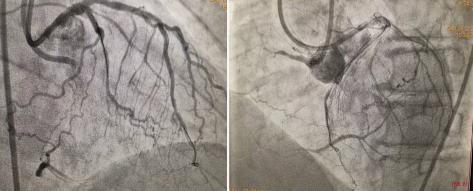

正向135cm1.8F微導(dǎo)管支持下再次嘗試GAIA3、PILOT200仍失敗,立即逆向送入150cm1.8F微導(dǎo)管至前降支遠(yuǎn)端,SION導(dǎo)絲塑小彎進(jìn)入預(yù)先選擇的間膈支,且順利通過(guò)間隔支至右冠閉塞段遠(yuǎn)端,微導(dǎo)管亦順利跟進(jìn)至右冠閉塞段內(nèi)。此時(shí),逆向?qū)Ыz如何進(jìn)入正向?qū)Ч軆?nèi)成為手術(shù)難題,既往多數(shù)病人皆因此而手術(shù)失敗。此時(shí)手術(shù)團(tuán)隊(duì)利用AGT技術(shù),正向指引導(dǎo)管內(nèi)送入Guidezilla延長(zhǎng)導(dǎo)管“出門迎客”,逆向微導(dǎo)管順利進(jìn)入正向延長(zhǎng)導(dǎo)管,此過(guò)程歷時(shí)約3分鐘,至此預(yù)示手術(shù)基本成功,右冠成功開(kāi)通。整個(gè)手術(shù)耗時(shí)70分鐘,造影劑量150ml。

圖2 AGT技術(shù)—正向Guidezilla延長(zhǎng)導(dǎo)管成功迎接逆向微導(dǎo)管